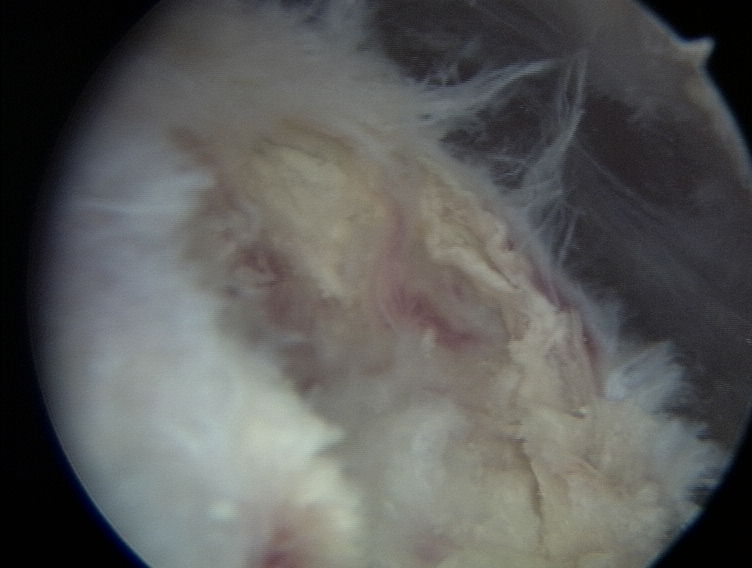

Kaletka maziowa podbarkowa (bursa subacromialis) w stanie chronicznego zapalenia.

Kaletka podbarkowa w nagłym stanie zapalnym.